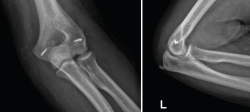

Esta lesión se encuentra dentro del espectro de las lesiones de la inestabilidad compleja de codo, aunque existen diferentes estudios donde se ha reportado la ausencia de lesión discernible en los estabilizadores ligamentosos(34,35,36). Esto comporta que el principio fundamental del tratamiento de estas lesiones es restablecer la anatomía de la fosa sigmoidea mayor y la coronoides. Restablecer la estabilidad del principal estabilizador del codo (articulación ulnohumeral) es suficiente para restablecer la estabilidad del codo (Figura 16).

Figura 16. Fractura luxación transolecraneana de codo tratada quirúrgicamente mediante la reducción abierta anatómica y fijación interna con placa preconformada de cúbito proximal.

Las placas preconformadas de cúbito proximal son de elección en este tipo de fractura(37,38,39,40). Esto es debido a que nos permiten realizar una reducción anatómica de todos los fragmentos y restablecer tanto la anatomía de la fosa sigmoidea mayor como de la coronoides. En ocasiones, puede ser necesario el uso de injerto óseo para la reconstrucción de la fosa sigmoidea mayor, dado que estas fracturas suelen ser consecuencia de impactos de alta energía y puede encontrarse mucha conminución del foco de fractura(41). Los errores más comunes durante el manejo quirúrgico de estas fracturas-luxaciones son(42):